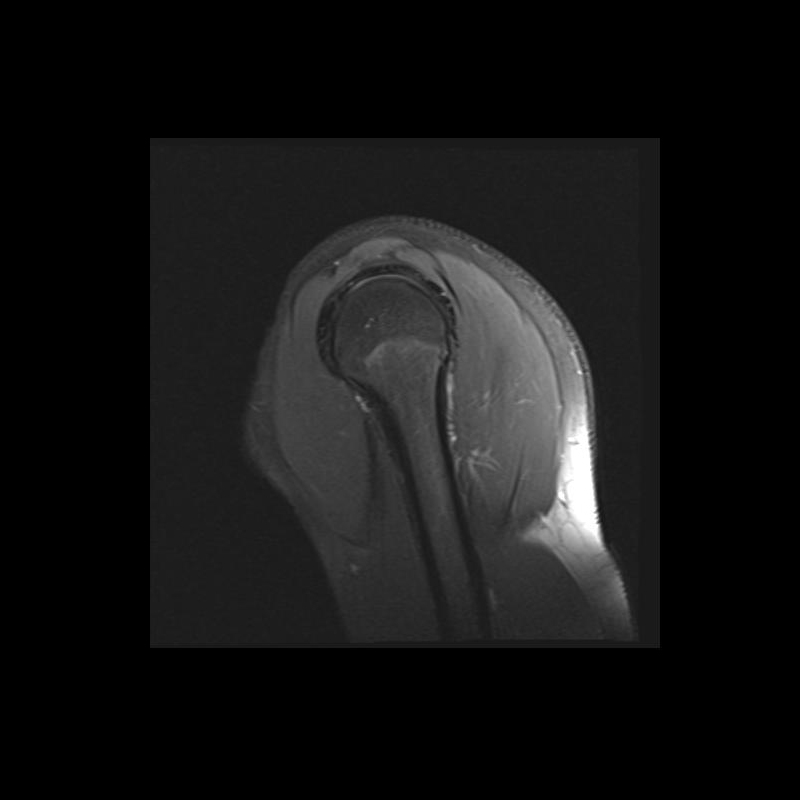

Shoulder MRI Anatomy